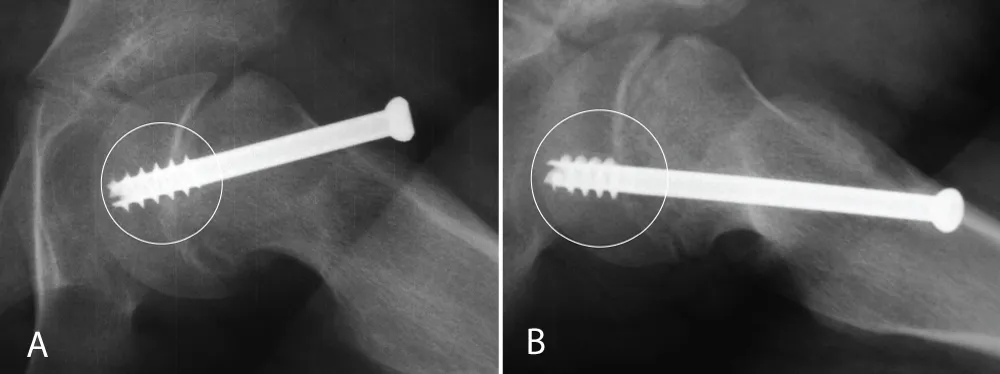

Approval from the Institutional Review Board was obtained before initiating this retrospective study. Between 1990 and 2002, patients with unilateral SCFE who had screw fixation and complete radiographs were included. Patients with atypical SCFE were excluded. Radiographs were assessed for physeal closure, and the time from the primary surgery until physeal closure was calculated. Closure was defined as 80% or more obliteration of the physis on both the anterior-posterior and lateral view [6]. The date of the first radiograph showing closure was set as the date of closure. If the time interval between the radiograph showing closure and the previous radiograph exceeded 6 months, patients were excluded since the date for closure in these patients was uncertain. Data regarding age, gender, degree of slip, and whether the triradiate cartilage was open or closed were collected. The position of the screw was assessed, and it was noted if the threads of the screw were crossing the physis or were contained entirely within the epiphysis (Figure 1A and B). In addition, the position of the screw head in relation to the lateral cortex was assessed. It was noted if the screw head was flush with the lateral cortex (≤ 5 mm exposure) or left proud (Figure 2A and B). Two orthopedic surgeons who were not involved in the care of any of the patients performed the radiograph assessments.

Figure 1: A and B: The threads of the screw crossing the physis, and (1B) the threads of the screw are contained entirely within the epiphysis.